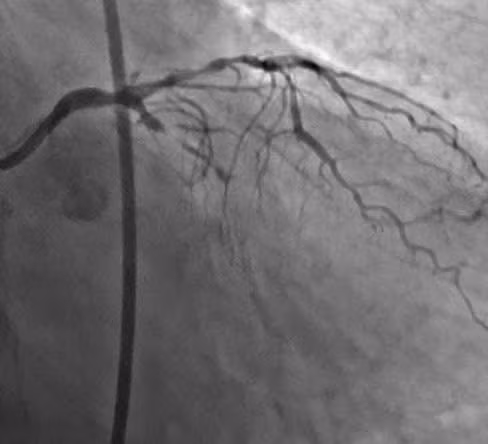

Tổn thương trước chụp động mạch vành - Ảnh BVCC

Kết quả chụp động mạch vành cho thấy động mạch liên thất trước (nhánh mạch máu quan trọng nhất của tim) bị hẹp khít tới 90%. Động mạch vành mũ đã bị tắc hoàn toàn mạn tính (CTO).